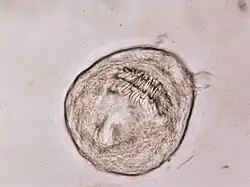

El cestodo adulto es una de las tenias más pequeñas, ya que su estróbilo (cuerpo del parásito) mide unos 5 milímetros de longitud (de 2 a 6 mm) y posee solo de 3 a 5 proglótides (segmentos). E. granulosus tiene cuatro ventosas en su escólex (cabeza), como todos los ciclofilídeos, y posee un característico un rostellum con 28 a 50 ganchos (usualmente 30 a 36), en doble hilera.